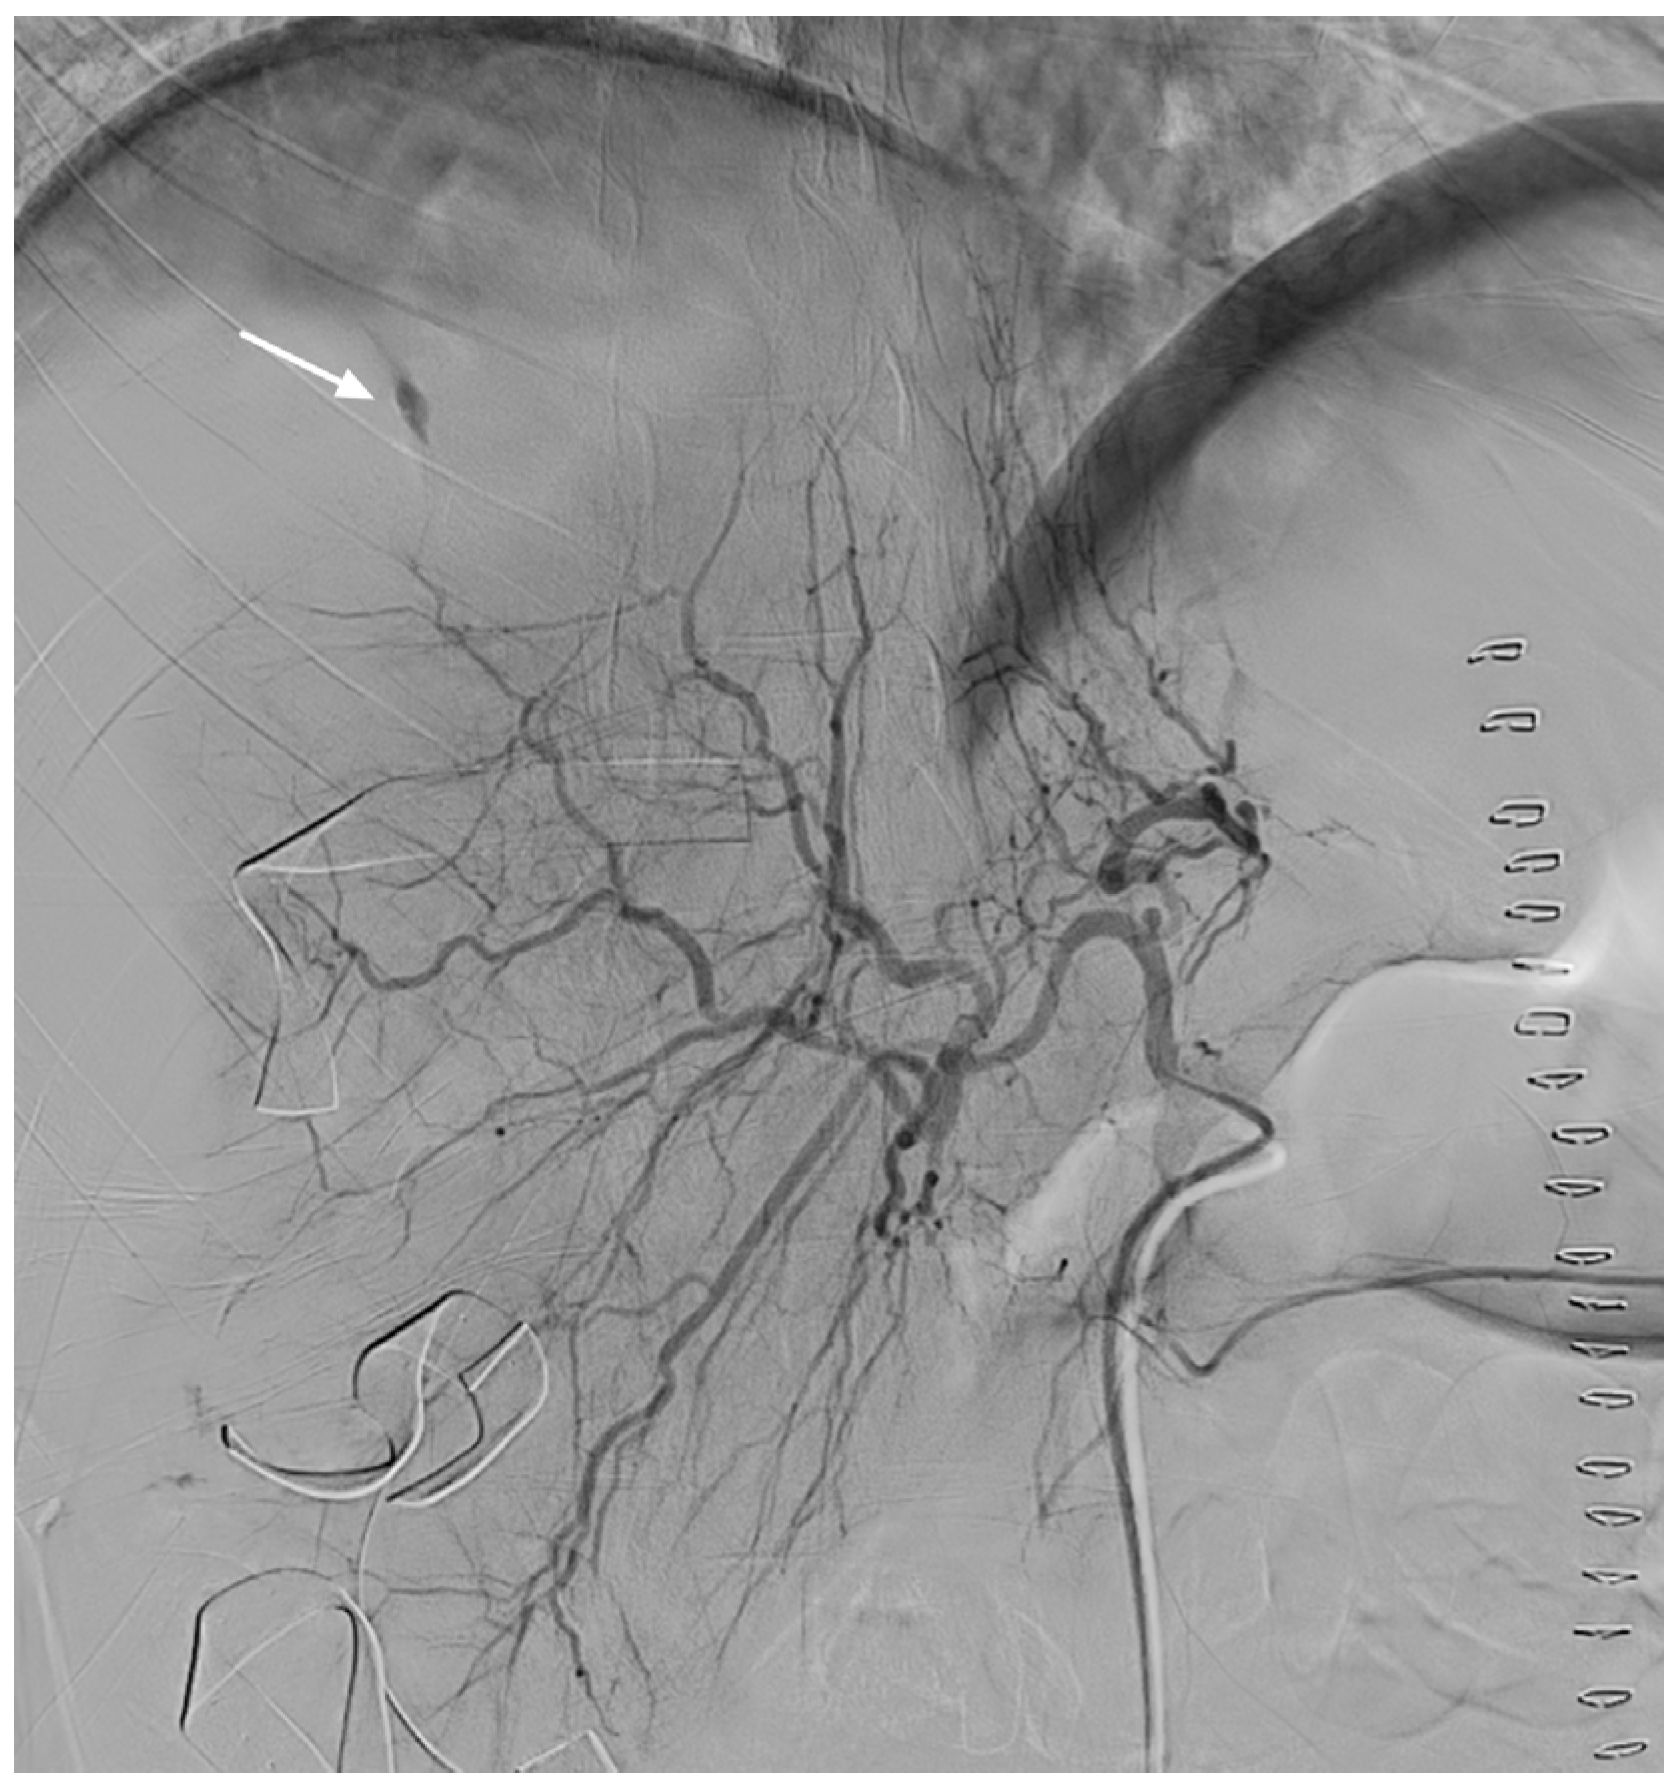

2. Case Presentation